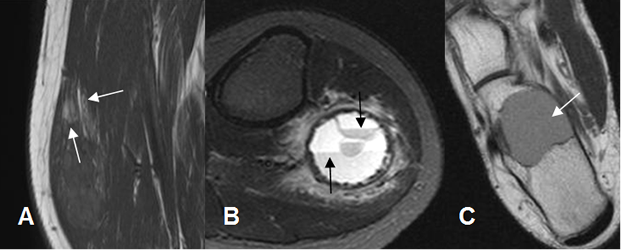

Fig 11. Lesiones fibrosas en RM.

A: RM sagital en T1, B: RM sagital en T2 y C: RM sagital en STIR. Múltiples lesiones redondeadas e hipointensas en todas las secuencias, por enfermedad metastásica de mama, con alto contenido fibroso.